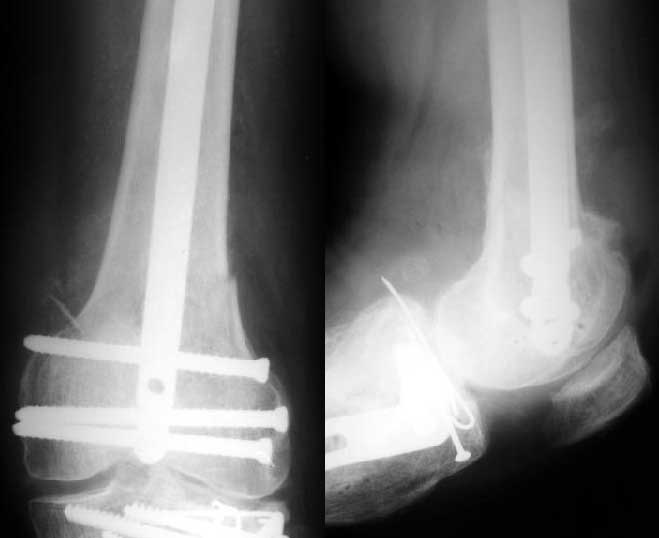

Винтами. Снимок в приложении.